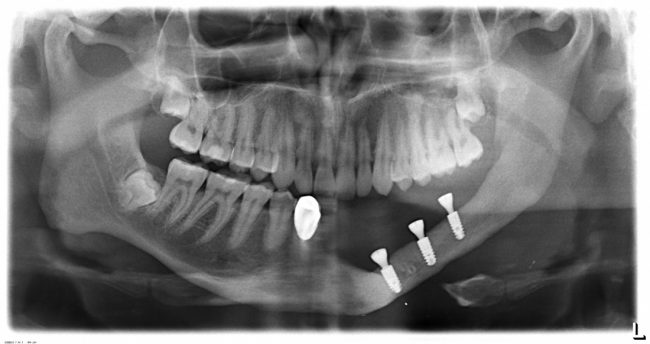

Итак, имплантаты установлены:

После операции и небольшой коррекции я вернул Ростиславу его съемный протез. Шеф назначил послеоперационную терапию. Осталось подождать интеграции, ориентировочно 4 месяца.

Через 4 месяца мы делаем контрольный рентгеновский снимок: